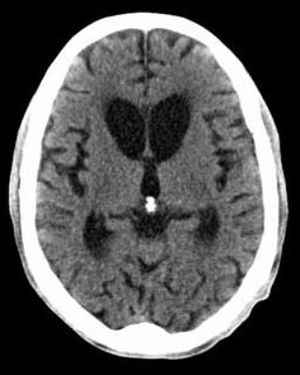

Huntington's disease is an autosomal dominant disease that is known by mutation on chromosome 4 with CAG trinucleotide repeates itself. Presentation is a young patient with a movement disorder, dementia, depression, aggression/psychosis. Key neurologic findings are atrophy of caudate nucleus seen on CT/MRI, decrease in GABA and Ach, increase in dopamine. Management is by using rivastigmine and tetrabenzine as they inhibit VMAT and increase neurotransmitter degradation by MAO. while haloperidol is used for psychotic symptoms and aggression. Note the atrophy of caudate nucleus on the MRI Image.